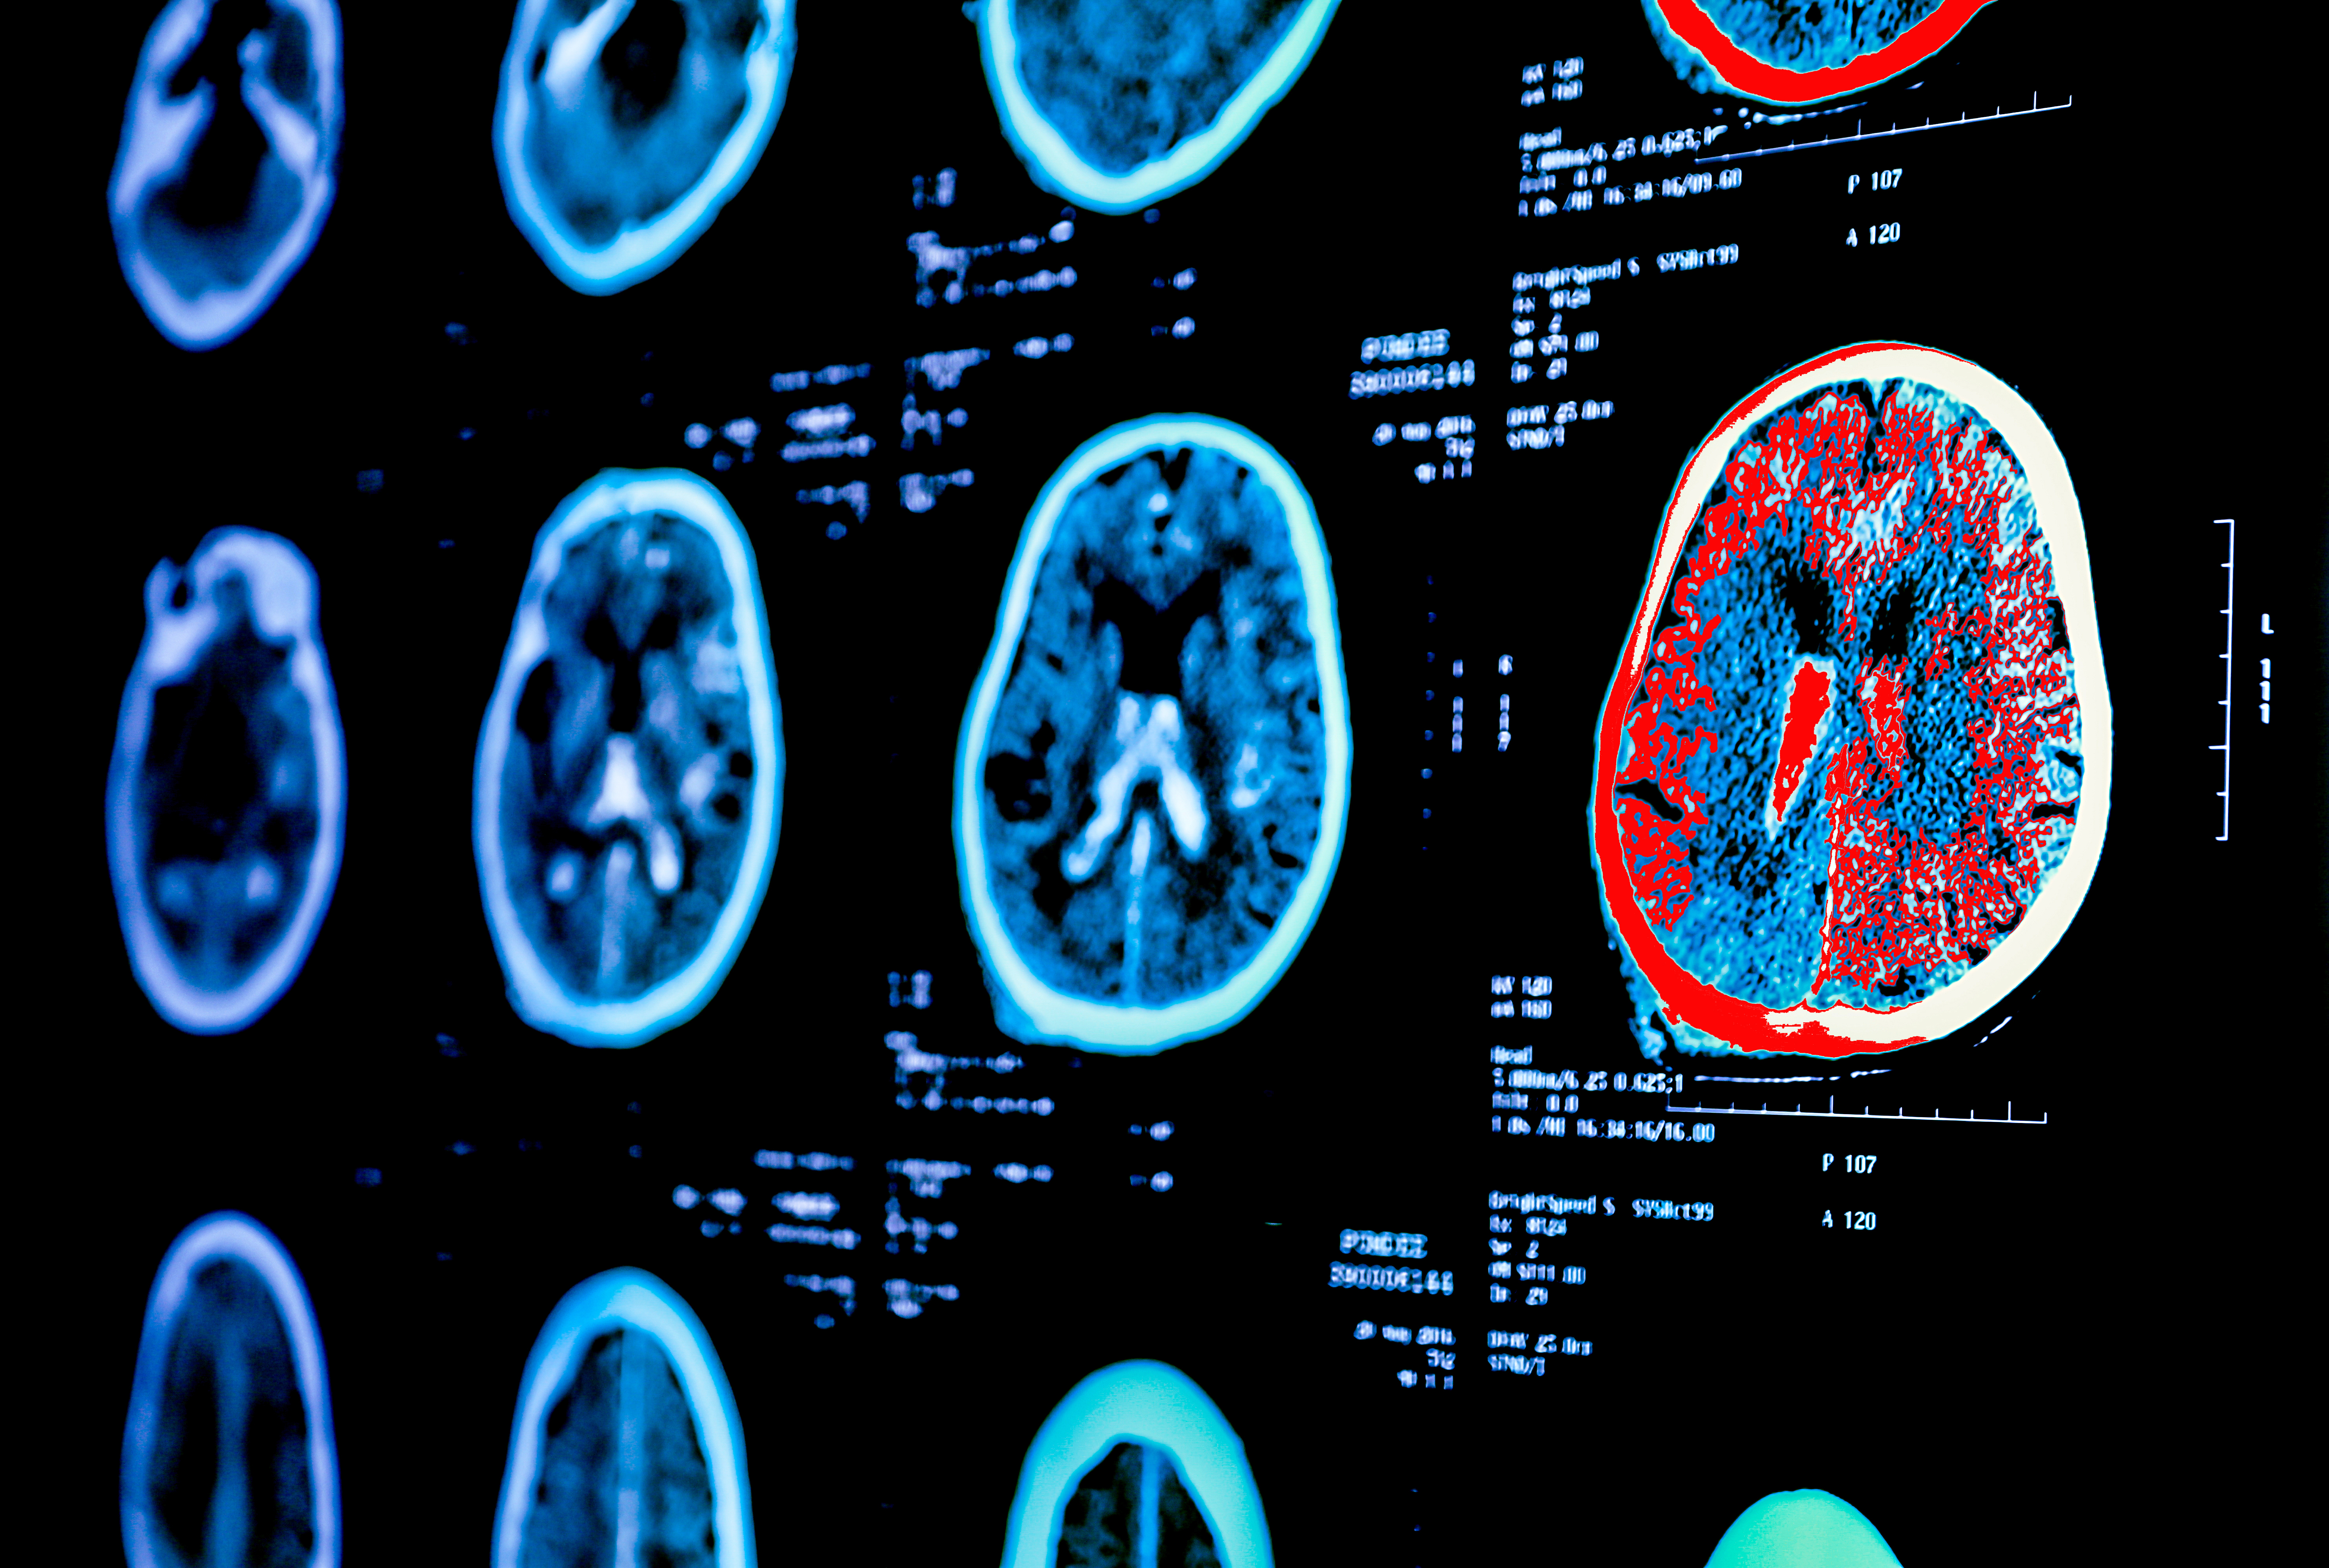

With nearly 30 years of neuroimaging experience in Alzheimer’s disease (AD), Perceptive is the imaging partner

you can rely on for end-to-end solutions that span the drug development lifecycle.

Specializing in PET and MRI imaging biomarkers, Perceptive delivers preclinical discovery through scalable

late‑phase global trial services with a unified operational and scientific framework.